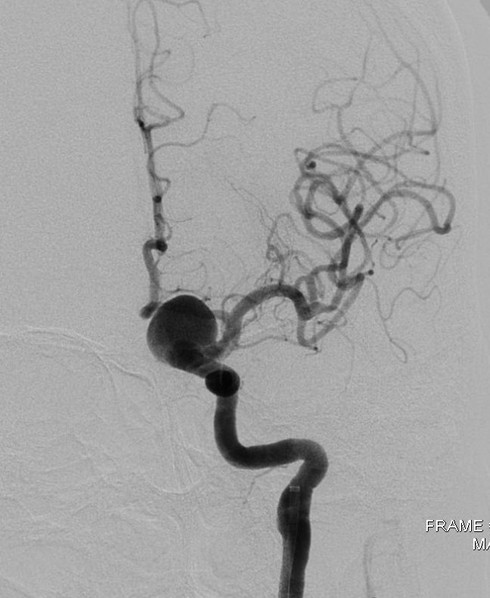

Động mạch não bị phình to |

Ngày 27/5/2015 bà V.T.V (62 tuổi, ở Biên Hòa, Đồng Nai) nhập viện trong tình trạng nhức đầu dữ dội và huyết áp cao. Khai thác, tiền sử bệnh nhân là cao huyết áp và nhức đầu thường xuyên. Qua thăm khám và hình ảnh chụp cắt lớp, các bác sĩ chẩn đoán: túi phình lớn động mạch cảnh trong trái ở não.

Bệnh viện đã tổ chức hội chẩn và nhanh chóng can thiệp cho bệnh nhân đặt một stent thay đổi dòng chảy ngang qua túi phình, qua đó túi phình dần dần co nhỏ và tắc. Thủ thuật thực hiện trên máy DSA hiện đại.